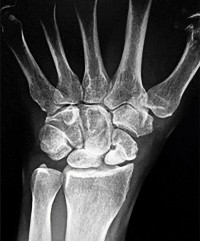

A 30-year-old male presents with a comminuted intra-articular fracture of the first metacarpal base.

What are the primary deforming forces acting on the metacarpal shaft in this injury?

Explanation

In intra-articular fractures of the thumb metacarpal base (Bennett and Rolando fractures), the palmar ulnar fragment remains attached to the anterior oblique ligament (beak ligament). The metacarpal shaft is pulled proximally, dorsally, and radially by the abductor pollicis longus (APL), while the adductor pollicis (AP) pulls the metacarpal head into the palm, resulting in the classic supination and adduction deformity.